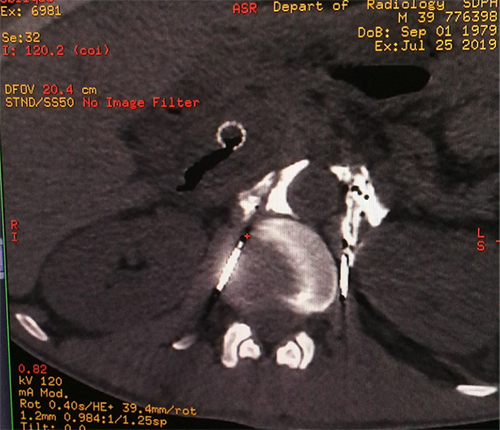

在医院影像科的配合下,疼痛科治疗团队通过CT设计穿刺进路,使得穿刺针到达了靶点位置。因患者曾经做过化疗和放疗,使得腹腔黏连加重,增加了手术难度,不利于毁损药物的扩散,但经过对穿刺针的反复调试,最终达到理想的效果。

腹腔神经丛毁损术是指将药物注入到腹腔神经丛所在部位,阻断支配内脏的交感神经,以缓解疼痛的一种方法。解剖学上,腹腔神经丛位于腹主动脉前缘,腹腔干及肠系膜上动脉之间。鉴于其周围有许多重要脏器结构,在CT引导下,穿刺针有效规避重要的脏器和血管精准到达神经丛。

穿刺到位造影剂分布良好